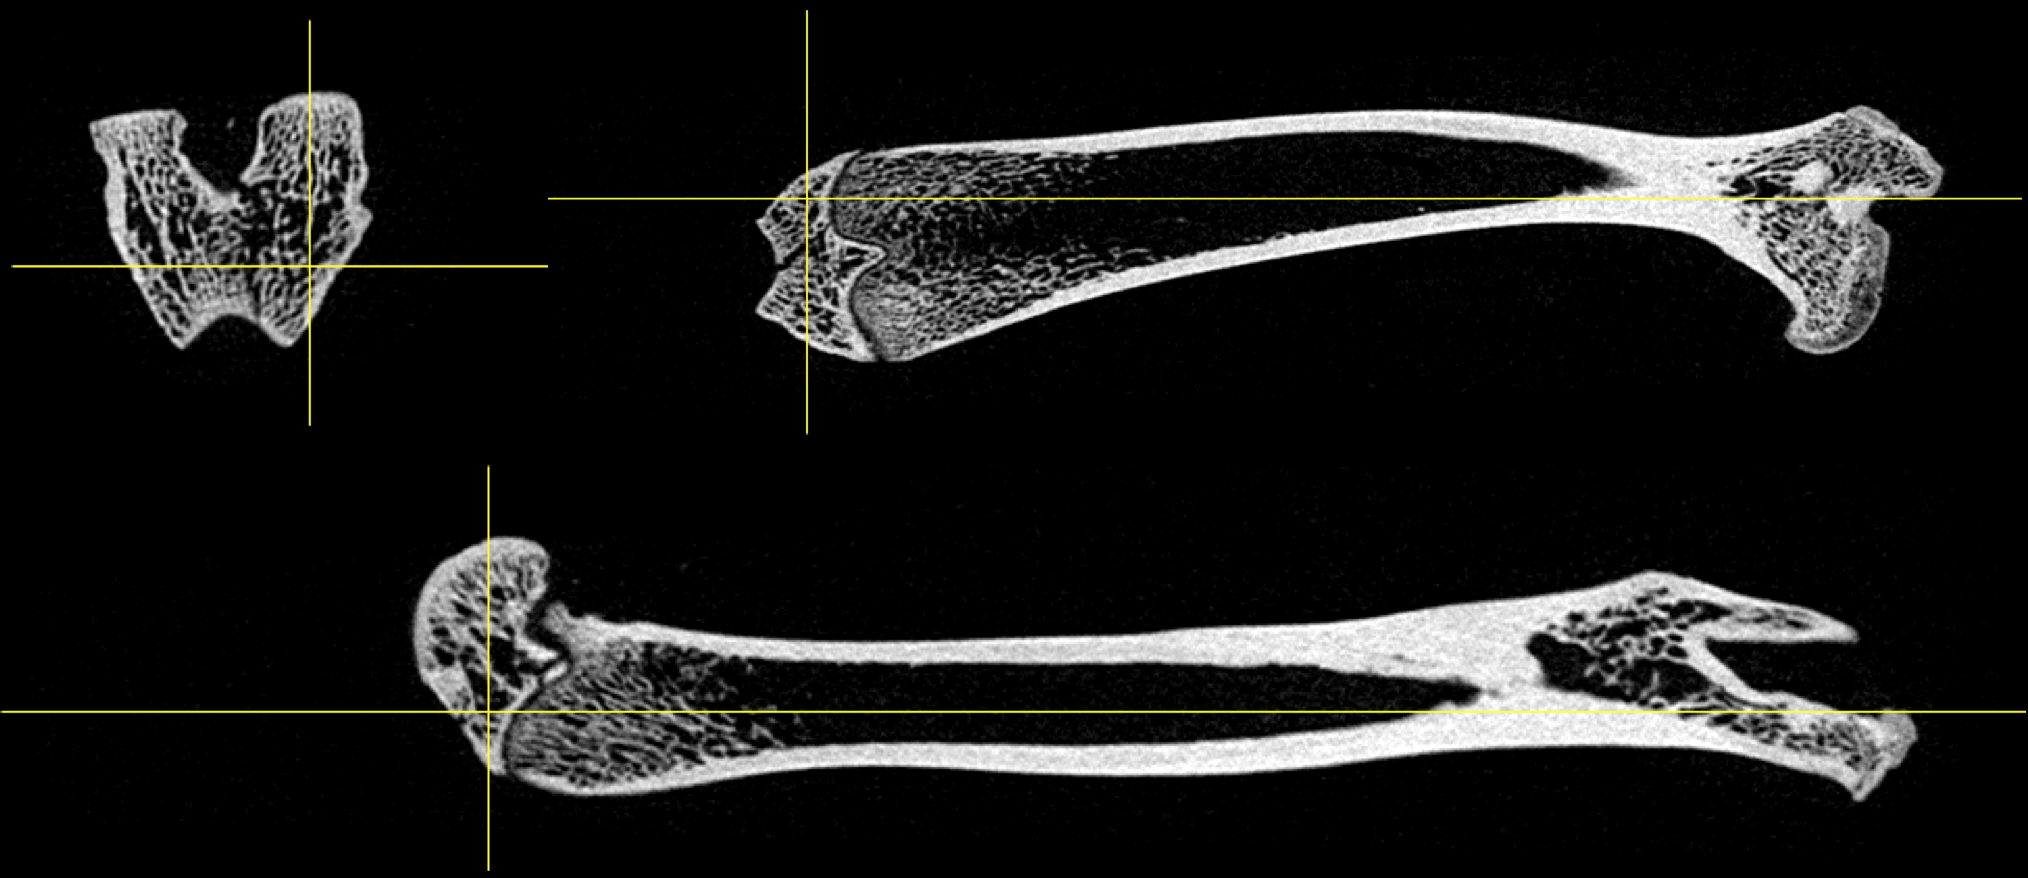

CASE 4: Ex-vivo bone study

workimg

• Courtesy of: Harbin Medical University, Harbin, China

Research objective: Ex-vivo study for trabecula bone structure

Animal model: Rat femur bone

Acquisition protocol: 112 s acquisition time, 80 kVp, 1 mA, 2000 projections, 1 bed position

Processing and reconstruction protocol: 0.06 mm isotropic voxel size